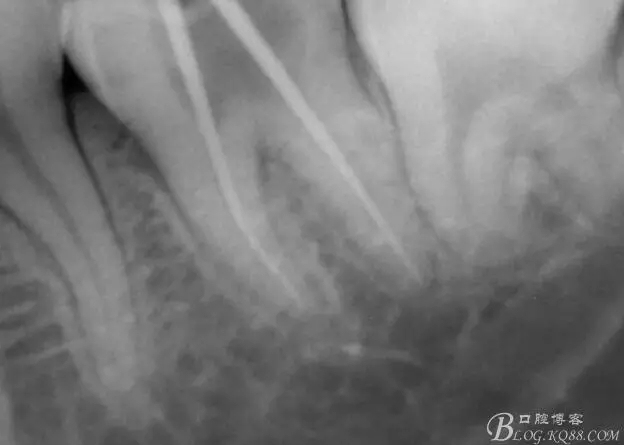

第二次復診,37叩(+-)。去除暫封物,沖洗,8號~12號挫疏通根管,15號挫用VDW電測確定根管工作長度,M : 18mm D :18mm,對應洞緣為標記點。其中近中根管感覺是頰舌兩根管,但進針感覺又是一根管,運用Crown Down Technique預備法,M3挫登士柏機動配合EDTA,1%次氯酸鈉,生理鹽水交替沖洗。紙尖干燥,封氫氧化鈣。